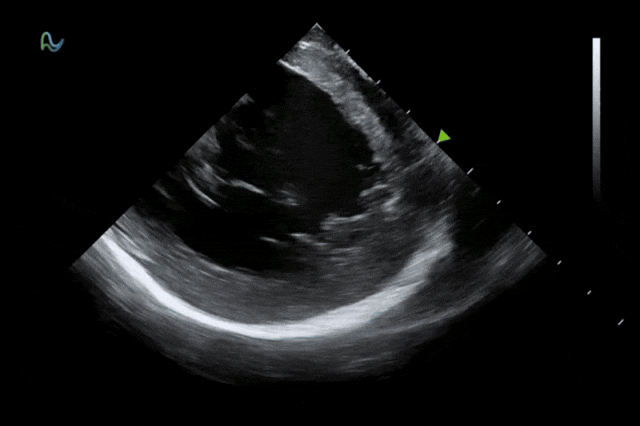

本次获批的ICE导管在全球首次采用了80阵元大孔径高密度探头设计,较传统普通的64阵元产品大幅度提升了成像分辨率、成像深度和图像对比度,可清晰辨识心脏细微结构和血流,为复杂手术给予更可靠的超声成像支持。同时,8F导管凭借更小的外径,显著提升导管顺利获得性和操控性,对病人创伤更小,尤其适合血管条件受限或小心脏患者;10F导管则凭借其优质的成像质量,为复杂心脏介入手术给予精准的影像引导。

心腔内超声(ICE)被誉为心脏介入手术的"黄金眼",能够顺利获得微创方式实时呈现心脏内部结构和血流成像,为房颤消融、左心耳封堵、先心病介入等手术给予精准成像导航。相较于传统影像手段,ICE具有无辐射、实时成像、操作灵活等显著优势,已成为国际指南推荐的核心诊断技术。